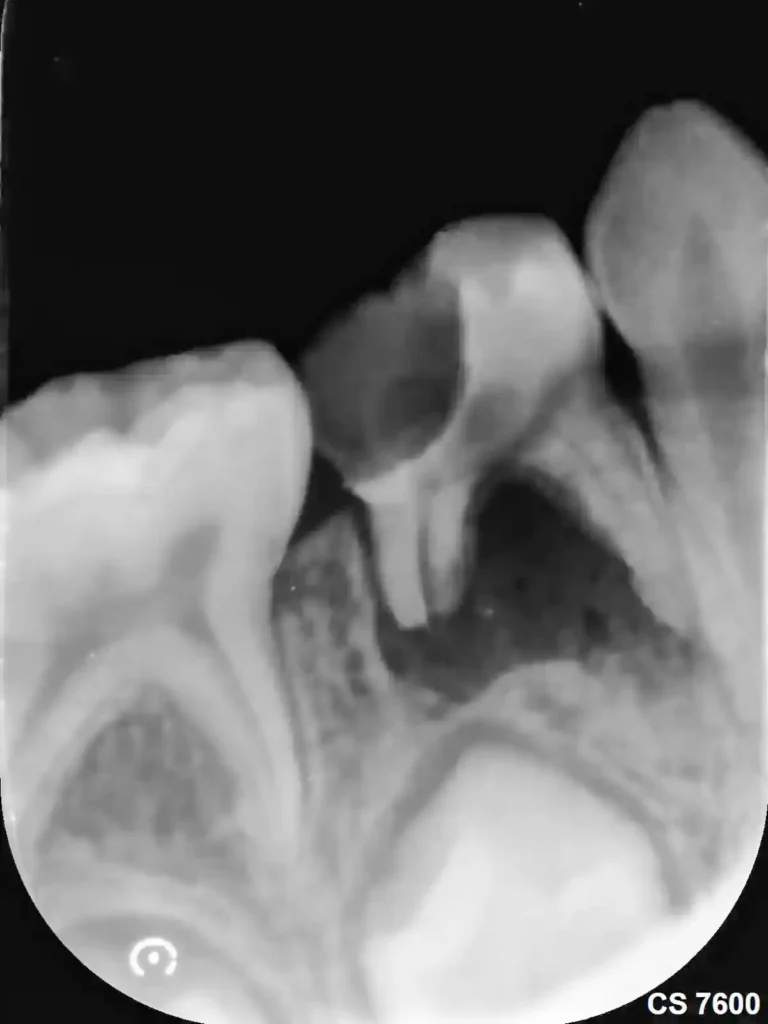

Un diente puede necesitar endodoncia por caries profunda, traumatismo, fractura, filtraciones antiguas o una infección que ya alcanzó la pulpa. En algunos pacientes aparece dolor espontáneo, sensibilidad intensa o dolor al morder. En otros, el problema avanza con menos síntomas y se detecta por cambios radiográficos, infección apical o destrucción interna que ya compromete la viabilidad del diente. La pregunta importante no es solo si duele, sino si el diente todavía puede conservarse bien y con qué tratamiento.

No todos los casos llegan en la misma etapa. Hay dientes con inflamación reversible, otros con daño pulpar irreversible y otros con infección ya extendida hacia la punta de la raíz. Mientras más tarde consulta el paciente, más importante se vuelve evaluar cuánta estructura queda, si hay fracturas asociadas, si existe infección apical y si el diente podrá sostener luego una restauración confiable. Conservar por conservar no es el objetivo. Conservar bien, sí.

En adultos, el objetivo suele ser conservar la pieza dentaria siempre que exista una base estructural y periodontal razonable. El tratamiento de conductos se indica cuando la pulpa está dañada o infectada y el diente todavía es recuperable. Si ya hubo un tratamiento previo y persiste inflamación o infección en el hueso alrededor del ápice, puede requerirse una apicectomía, es decir, una cirugía sobre la punta de la raíz para retirar el tejido infectado y sellar el extremo radicular.

Qué se evalúa antes de decidir

Antes de indicar una endodoncia, hay varias preguntas que importan: si la pulpa está inflamada o infectada, si existe lesión apical, cuánto tejido remanente queda, si hay fracturas, qué restauración necesitará después y cuál es el pronóstico real del conjunto. En niños, además, se suma el análisis del tipo de diente, su rol en el desarrollo y el impacto que una extracción podría tener sobre la erupción futura.